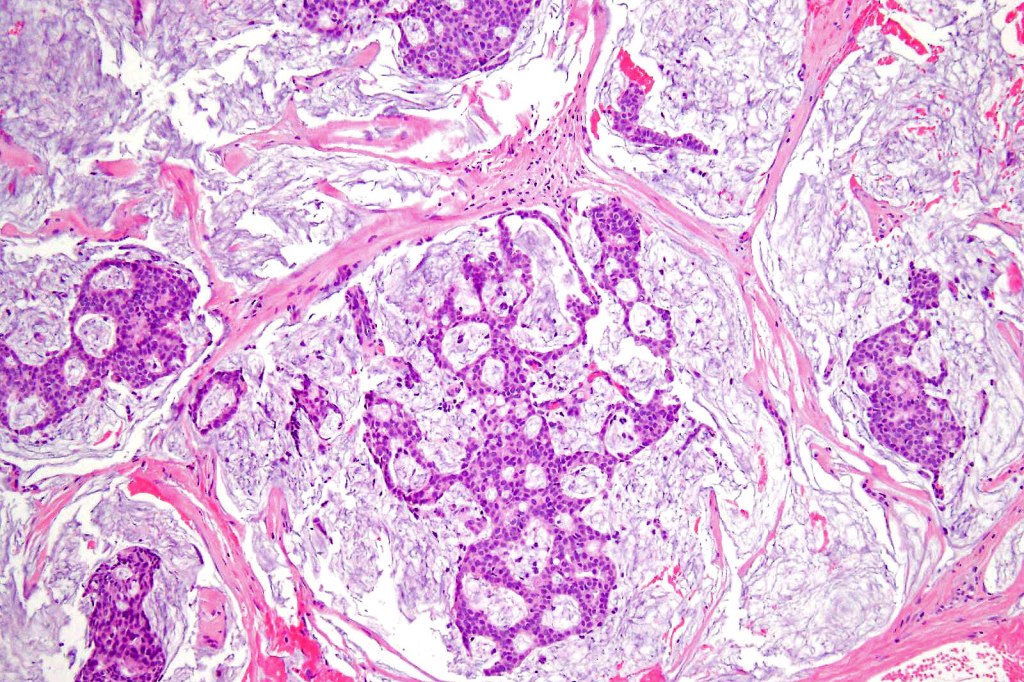

•Mucinous carcinoma is characterized by epithelial islands dispersed in a rich mucinous stroma

•EMPSGCa– multiple nodules of uniform epithelial cells with vesicular nuclei & small nucleoli

•In situ component sometimes evident

•+/- intracytoplasmic mucin

•Cyst formation sometimes evident

•Papillae & cribriform pattern sometimes evident

•+/- invasive mucinous carcinoma (50%)